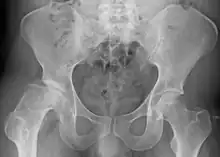

| Radiograph of a person with Legg–Calvé–Perthes disease | |

X-rays of the hip may suggest and/or verify the diagnosis. X-rays usually demonstrate a flattened, and later fragmented, femoral head. A bone scan or MRI may be useful in making the diagnosis in those cases where X-rays are inconclusive. Usually, plain radiographic changes are delayed six weeks or more from clinical onset, so bone scintigraphy and MRI are done for early diagnosis. MRI results are more accurate, i.e. 97–99% against 88–93% in plain radiography. If MRI or bone scans are necessary, a positive diagnosis relies upon patchy areas of vascularity to the capital femoral epiphysis (the developing femoral head).[11]